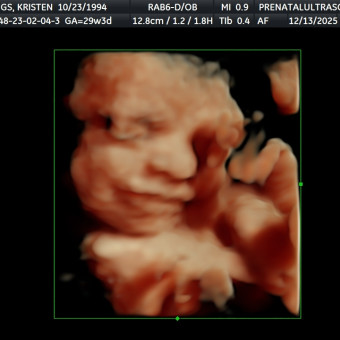

Baby Girl Iddings

Kristen Iddings

Orlando, FL

February 19, 2026